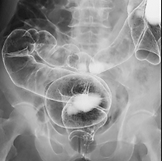

■血管造影装置

キャノンメディカルシステムズ:infinix celeve-I infx-8000f

左腕シャント血管の造影画像

血管にカテーテルを挿入した後に造影剤を注入して、血管の狭窄や血流状態の検査します。

血管を拡張する治療も行っています。

シャントの治療(経皮的血管形成術)について